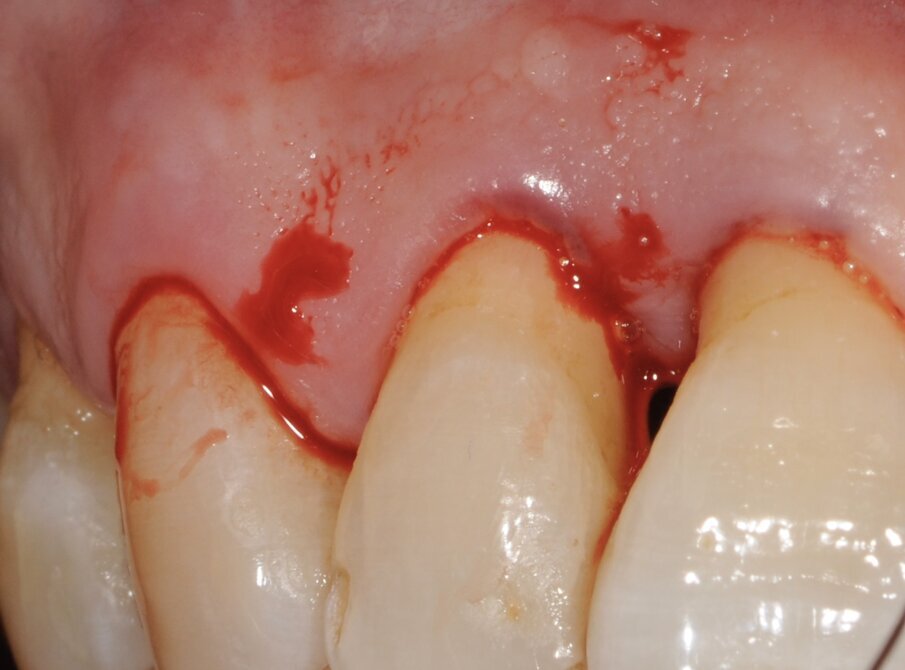

Un paziente di 56 anni non fumatore viene riferito alla nostra osservazione per il trattamento della parodontite. Dopo aver effettuato la diagnosi (parodontite generalizzata Stadio III, Grado C) il paziente è sottoposto a due sedute di scaling sopra gengivale (step 1) e successivamente a 4 sedute di debridement sotto gengivale effettuato con strumenti ultrasonici e manuali (step 2). Al momento della rivalutazione si registra un miglioramento degli indici di placca e di sanguinamento (FMPS e FMBS ≤ 20%) e una riduzione di tutte le tasche parodontali (PD<4 mm) in ciascun sestante a eccezione del secondo sestante. In questa regione si registra una tasca residua con PD = 6 mm a carico dell’elemento 1.1, associata a un riassorbimento osseo radiografico prevalentemente orizzontale (Figg. 1, 2). Considerando il miglioramento di tutti i parametri e degli indici parodontali e la presenza di una tasca con PD = 6 mm a carico di un solo elemento dentario si decide di ritrattare l’elemento 1.1 con terapia non chirurgica (step 3). La nuova ristrumentazione è stata effettuata seguendo il protocollo Clean&Seal che prevede l’associazione di ipoclorito di sodio stabilizzato con amminoacidi e acido ialuronico reticolato ad alto peso molecolare in combinazione con il debridement sotto gengivale. Dopo anestesia locale, è stato applicato all’interno della tasca l’ipoclorito di sodio stabilizzato con amminoacidi e lasciato agire per circa 60 secondi (Fig. 3). Successivamente è stata effettuata la strumentazione sotto gengivale mediante l’utilizzo di strumenti ultrasonici e manuali (Figg. 4, 5). Alla fine della procedura di strumentazione, nella tasca è stata effettuata un’irrigazione con soluzione salina sterile e la procedura di applicazione di ipoclorito di sodio e di strumentazione meccanica è stata ripetuta per 4 volte. Un fattore critico per garantire un risultato migliore è di evitare di instillare qualsiasi soluzione a base di clorexidina nella tasca, in quanto inibisce l’adesione cellulare. Alla fine del trattamento meccanico è stato inserito l’acido ialuronico reticolato ad alto peso molecolare all’interno della tasca per stabilizzare il coagulo e accelerare la guarigione (Fig. 6). Il controllo clinico è stato effettuato dopo 6 settimane dal trattamento con completa chiusura della tasca (Fig. 7).